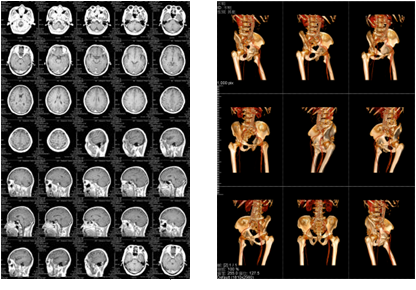

該三甲醫院放射科負責日常CT、核磁共振影像的輸出,平均的日打印量在1000張左右。在導入解決方案前,該放射科的影像輸出使用干式膠片打印傳統膠片,輸出設備價格不菲,而且傳統膠片價格更是高昂。另外,傳統膠片不能實現彩色輸出,醫生必須在背光板上進行診斷,膠片本身還含有重金屬等有毒物質,污染環境。為此,柯尼卡美能達向專業供應商采購了DICOM轉換服務器和符合醫院要求的打印膠片紙,可實現三維打印,打印的影像可直接在自然光下觀看,便于醫生診斷;膠片紙的成本是傳統膠片的三分之一而且不含毒物質,既節省成本又綠色環保。

膠片紙輸出樣張示意